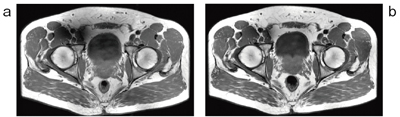

被検体ごとの最適なRF送信を行うため,B1 mapを作成する際にBloch-Siegert shiftを採用している。従来の方法などでは,T1値の影響を受けやすいため,TRを延長しないとその影響を除くことができず,B1 mapの撮像時間が延長してしまっていた。一方で,Bloch-Siegert shiftを用いたB1 mapは,原理的にT1値の影響を受けにくいため,撮像時間の延長はない。また,この手法では,被検体の形状と体組成の両方を考慮し,より正確なB1 mapの作成が可能である。図3に示すように,従来法と比較すると,より均一なRF送信を行うことが可能になる。Discovery MR750w 3.0Tでは“QD” “Preset” “Optimized”の3つのRF送信モードを有している。Optimizedモードでは,Bloch-Siegert shiftを用いたB1 mapにより,自動的に求められた位相比,振幅比に加えて,さらにマニュアル“RF Drive Settings”で微調整が可能であり,さまざまな状況に対応できるシステムになっている。また,均一性という観点からは,RF均一性はもちろんのこと,静磁場の均一性も必須である。優れた磁場均一(0.27ppm@40cmDSV, typical値)とこのMulti Driveの効果により,図4に示すように均一な脂肪抑制効果,および歪みの少ないhigh b-value DWIが可能となる。

![]() 図4 Discovery MR750w 3.0Tの躯幹部領域の撮像例 a:乳腺領域DWI(上:b=1000s/mm2,下:b=2000s/mm2) b:前立腺DWI(上:b=1000s/mm2,下:b=2000s/mm2) |